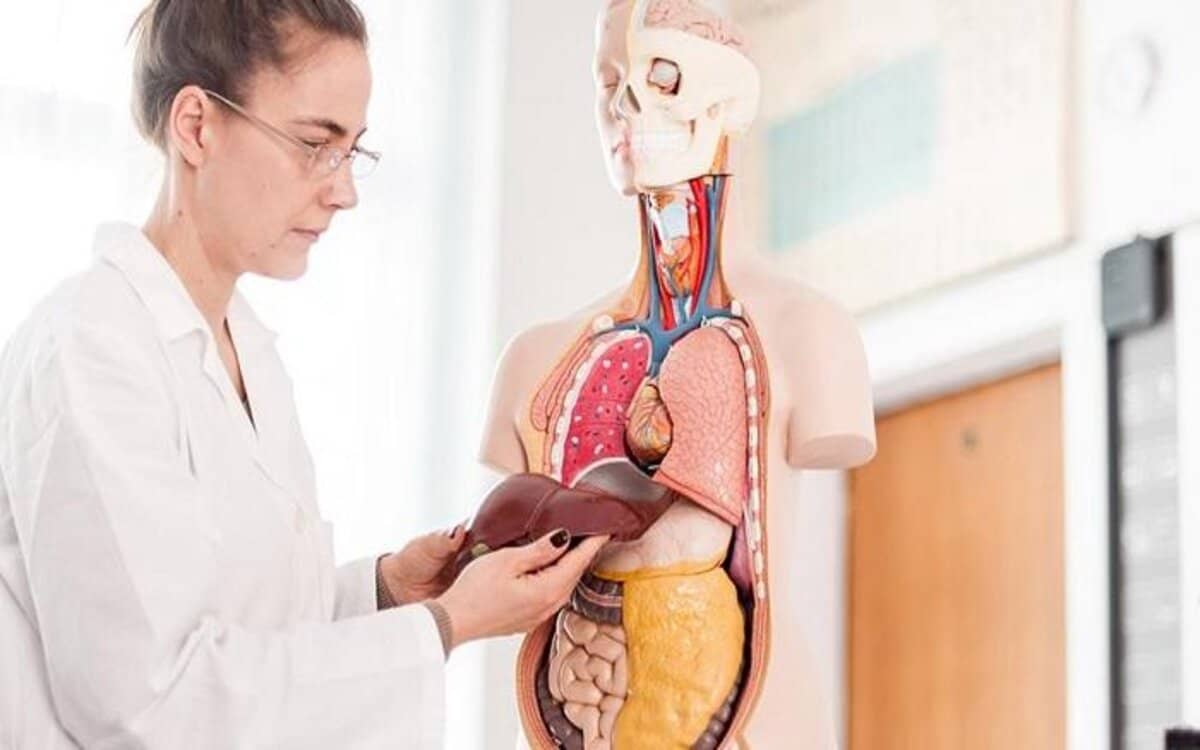

إنزيم alt هو ناقلة أمين الألانين، ويُفرزه الكبد بمستويات طبيعية ليتمكن من أداء وظائفه في التخلص من سموم الجسم، وإنتاج المادة الصفراء التي تساعد في عملية الهضم، وتخزين جيد للعناصر الغذائية المهمة والحديد، والمساعدة في صناعة البروتينات.

وتحليل alt ast، هو فحص لمستوى أحد إنزيمات الكبد المسمى بـ”إنزيم أسبارتيت أمينوترانسفيريز”، ويوجد هذا الإنزيم في مختلف أعضاء الجسم الداخلية خاصة الكبد والكلى والقلب، وعند تعرض أحد هذه الأعضاء إلى مشكلة ما، يؤدي إلى تسربه إلى الدم وارتفاع مستواه.

ولذلك يفيد اختبار مستوى انزيمات الكبد alt ast في الدم، في الكشف المبكر عن أمراض الكبد، فهو من التحاليل الهامة التي قد يطلبها الطبيب للكشف عن أمراض الكبد.